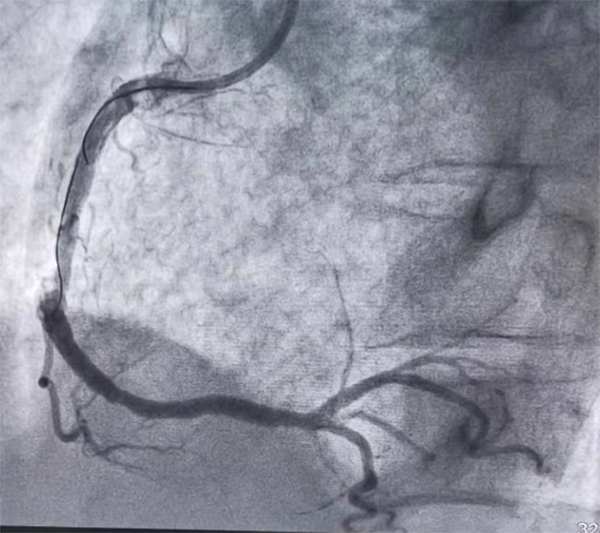

從12:22分進入雒容鎮中心衛生院大門到12:50分轉出僅用時28分鐘。下午13:06分,病人安全轉運到了柳州市人民醫院心導管室,立即施行急診冠狀動脈造影+支架植入術。造影提示覃阿公的右冠狀動脈完全閉塞,術中開通了閉塞的血管,血流恢復正常。覃阿公胸痛緩解,生命征穩定,在柳州市人民醫院住院后病情平穩出院,回到社區,接下來雒容鎮中心衛生院家庭醫生團隊跟進隨訪,進行健康教育、康復和長期用藥及注意事項的指導,完成胸痛救治閉環。這是雒容鎮中心衛生院胸痛救治單元成立以來完成的39個急性心梗病人其中一位。

血管再通